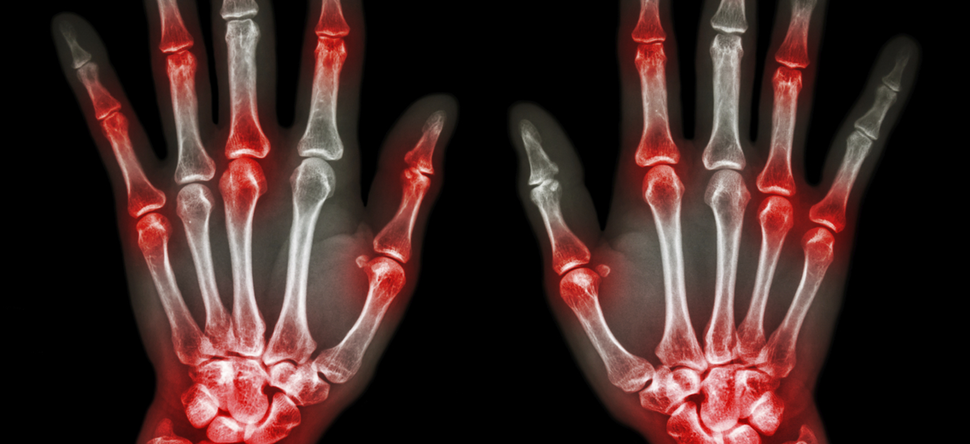

Immunology, Allergy, and Rheumatology

Pathogenesis of allergic, Th17, autoimmune, and fibrotic lung diseases; health care outcomes of arthritis and arthritis therapy; molecular control of mitosis and cytokine signaling; vaccination against substances of abuse.